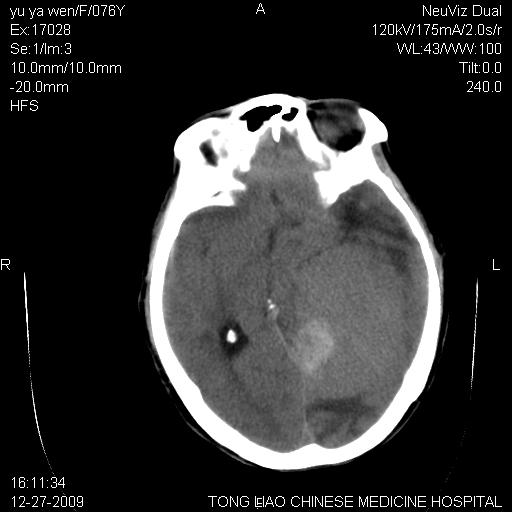

以下是引用lizhiguang在2009-12-27 19:06:00的发言:[br]脑膜瘤

以下是引用zhao_bin2008在2009-12-27 20:34:00的发言:[br]考虑脑膜瘤,伴肿瘤出血,建议增强检查

以下是引用zsl6918在2009-12-27 19:28:00的发言:[br]建议对症治疗后强化检查,考虑脑膜瘤可能性大。